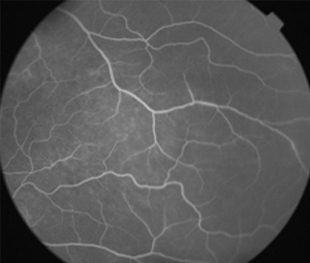

Angiografía OI

- Angiografía: teñido arterial, escape capilar, más tardíamente, no perfusion arteriolar y venular con teñido de las paredes vasculares y dilatación venosa.